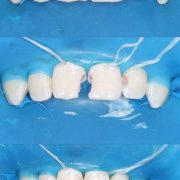

- Лечение пульпитов с глубокими кариозными полостями с помощью металлических коронок.

- Консультация, составление плана и лечение в условиях наркоза.